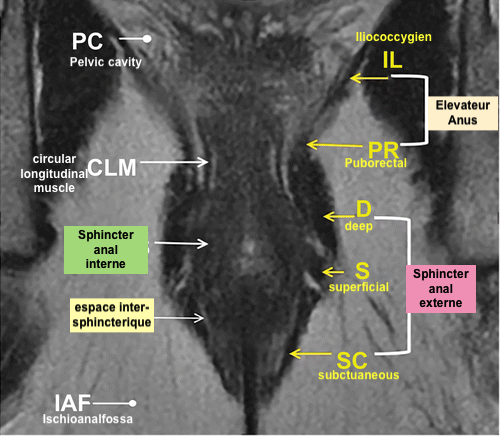

Anatomie et Classification

- Muscle releveur de l’anus comprenant le pubo-rectal et l’ilio-coccygien

- Sphincter Interne

- Sphincter Externe